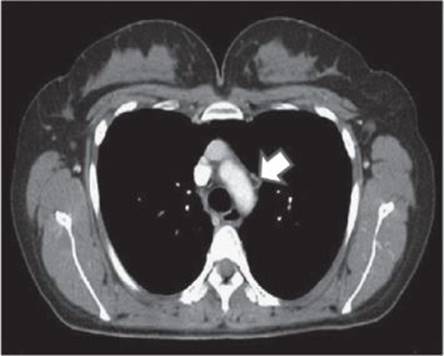

Nine months after the second surgery, a routine CT scan revealed mediastinal lymph nodes, measuring 40, 21, and 24mm (Fig. 15.3). The patient declined a biopsy.

Fig. 15.3